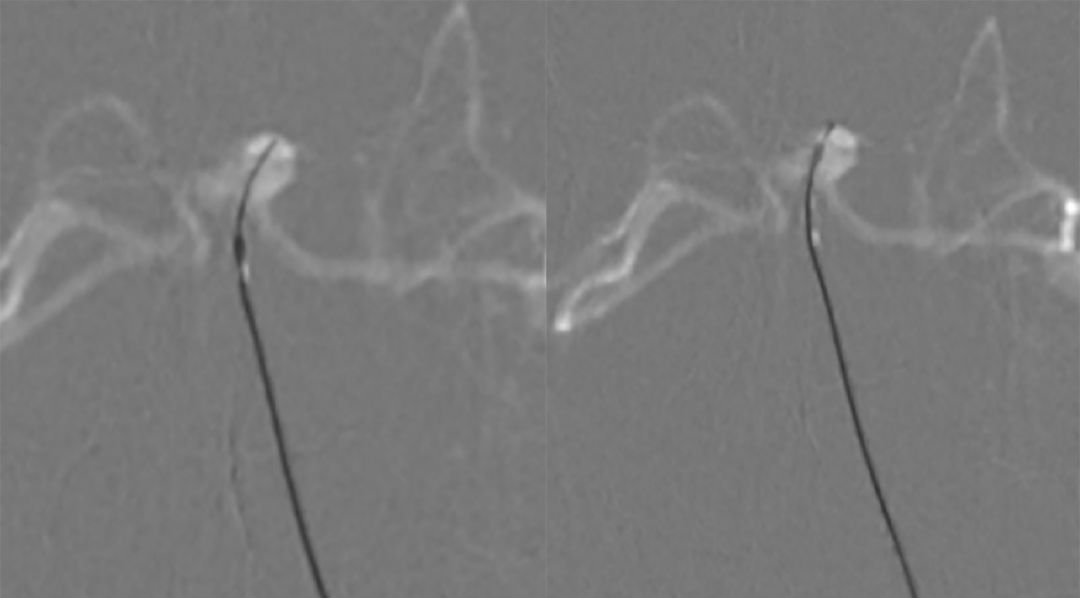

5. 调整至合适的工作角度后,路径图引导下,Synchro(0.014,200 cm)微导丝携Echelon-10微导管超选进入左侧小脑上动脉瘤(图10微导丝到位,图11微导管到位)。

图10 微导丝到位 图11 微导管到位

6. 多个投射角度辅助下,将数枚弹簧圈枚植入动脉瘤内(图12)。

图12

7. 术后造影显示动脉瘤完全栓塞,载瘤动脉通畅(图13)。

图13